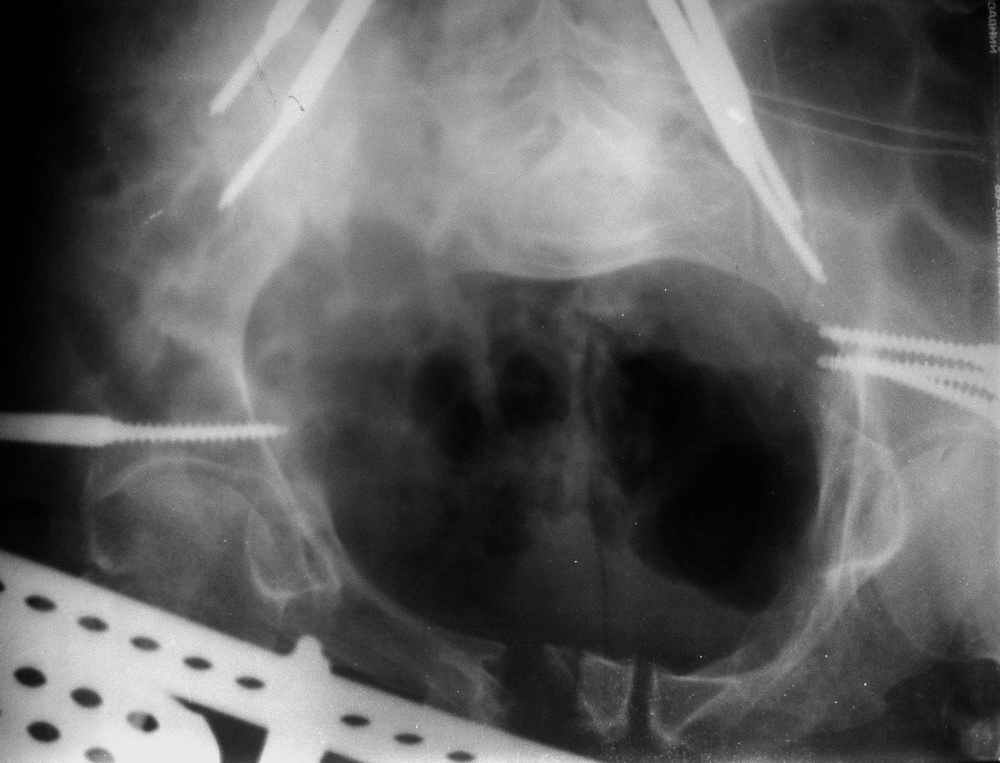

Пример лечения стабильной деформации с вертикальным смещением половины таза.

Исходная картина

отеотомия передних и задних отделов, дистракция аппаратом